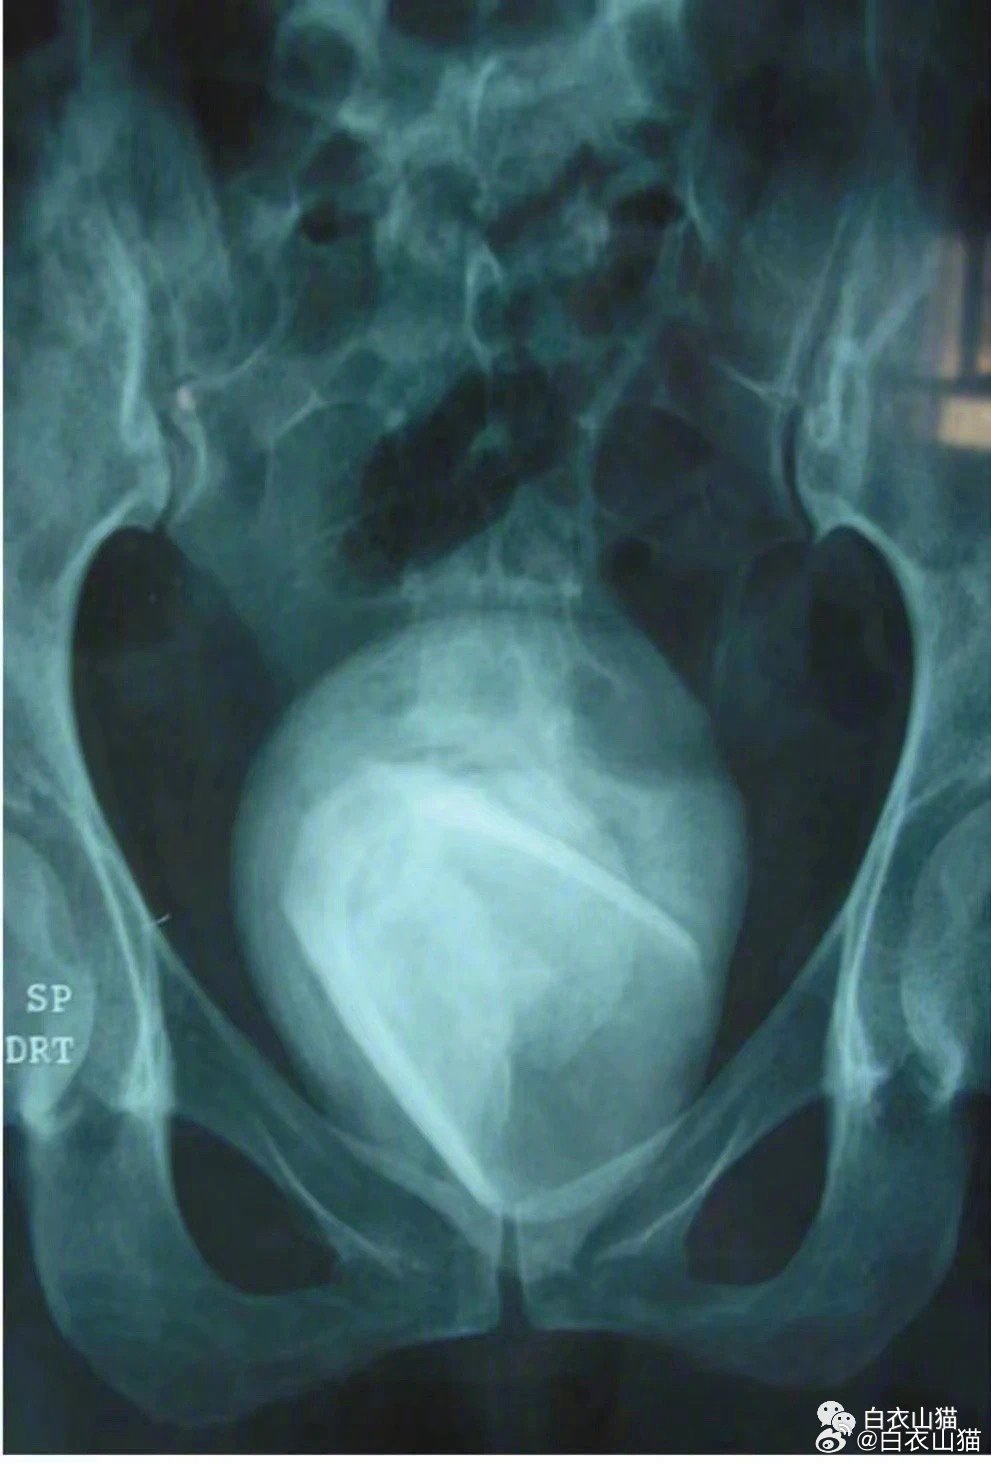

图片1:成人阴道异物穿透膀胱,导致膀胱阴道瘘。

上面就是一个阴道膀胱瘘的病人的图片。